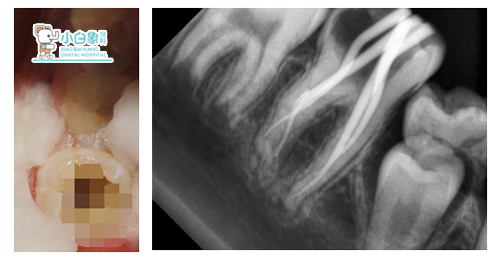

治疗过程:46去暂封,拔髓,测远中颊根长24mm,

远中舌根长22mm,近中颊舌根22mm,冲洗根管,

隔湿干燥,根管内置牙胶尖+根管糊剂充填根管,